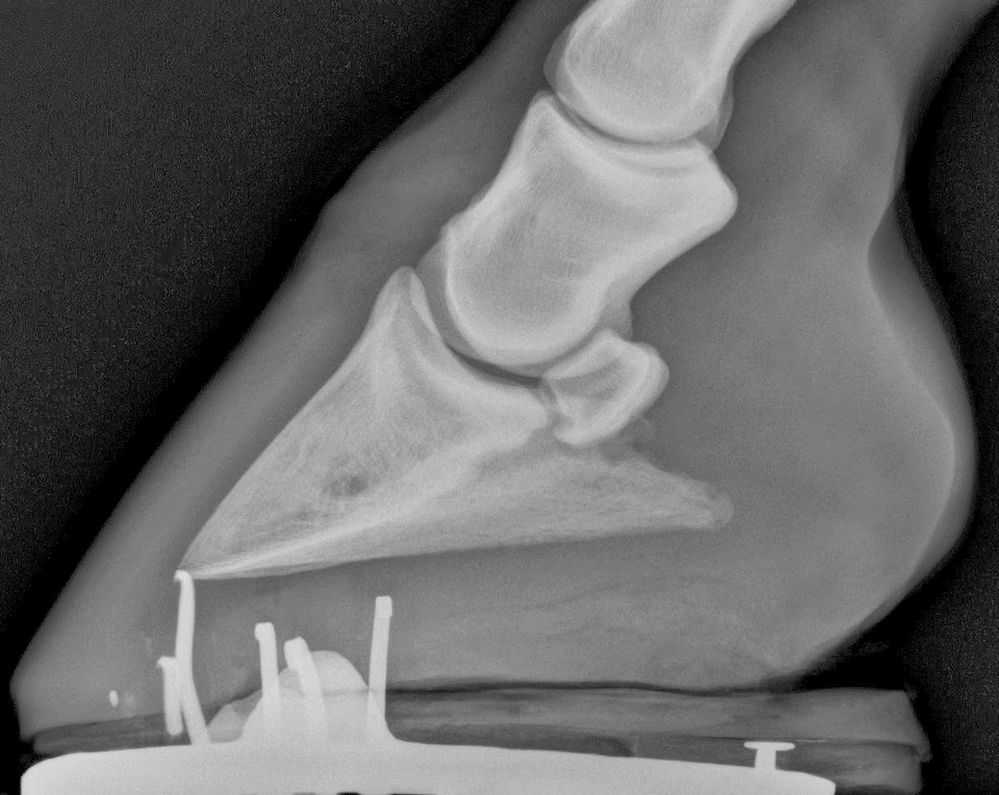

From www.researchgate.net

photograph of the xray film of the fetlock, pastern and coffin joints.... Download Scientific Coffin Joint Lameness Treatment Lameness is infrequent but may occur if infection, an abscess, or displacement of the coffin bone is also present. Many cases of mystery lameness, that may once have been attributed to navicular syndrome, are now thought to be caused by. Low ringbone develops around the joint between the coffin bone and the short pastern bone, just within the top of. Coffin Joint Lameness Treatment.